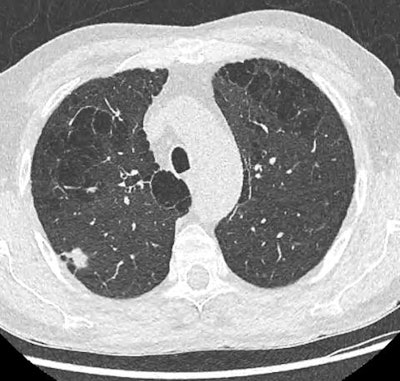

After years of hesitation, France's national Health Authority (Haute Autorité de Santé, HAS) decided in February 2022 to launch pilot programs for lung cancer screening using low-dose thoracic CT. This is not yet a population-based screening program as is the case for breast cancer, for example, but it is a very important step, according to thoracic experts.

Certain methodological questions remain unresolved -- for example, the precise definition of the target population (i.e., the population for which the benefit/risk ratio of screening is maximal), the duration and optimal rhythm of screening, the problem of overdiagnosis (i.e., a cancerous nodule which, if left untreated, would not alter the life expectancy of the patient), or the role of artificial intelligence (AI) software in assisting in the detection and characterization of nodules.

First of all, radiologists must be aware of their responsibility in an undertaking that could save 5,000 lives each year. As early diagnosis is based solely on low-dose thoracic CT, radiologists are on the front line and have a duty to train in screening. The SFR and the Thoracic Imaging Society (Société d'Imagerie Thoracique, SIT) have set up a teaching program open to all radiologists wishing to be trained in the interpretation of screening scans.